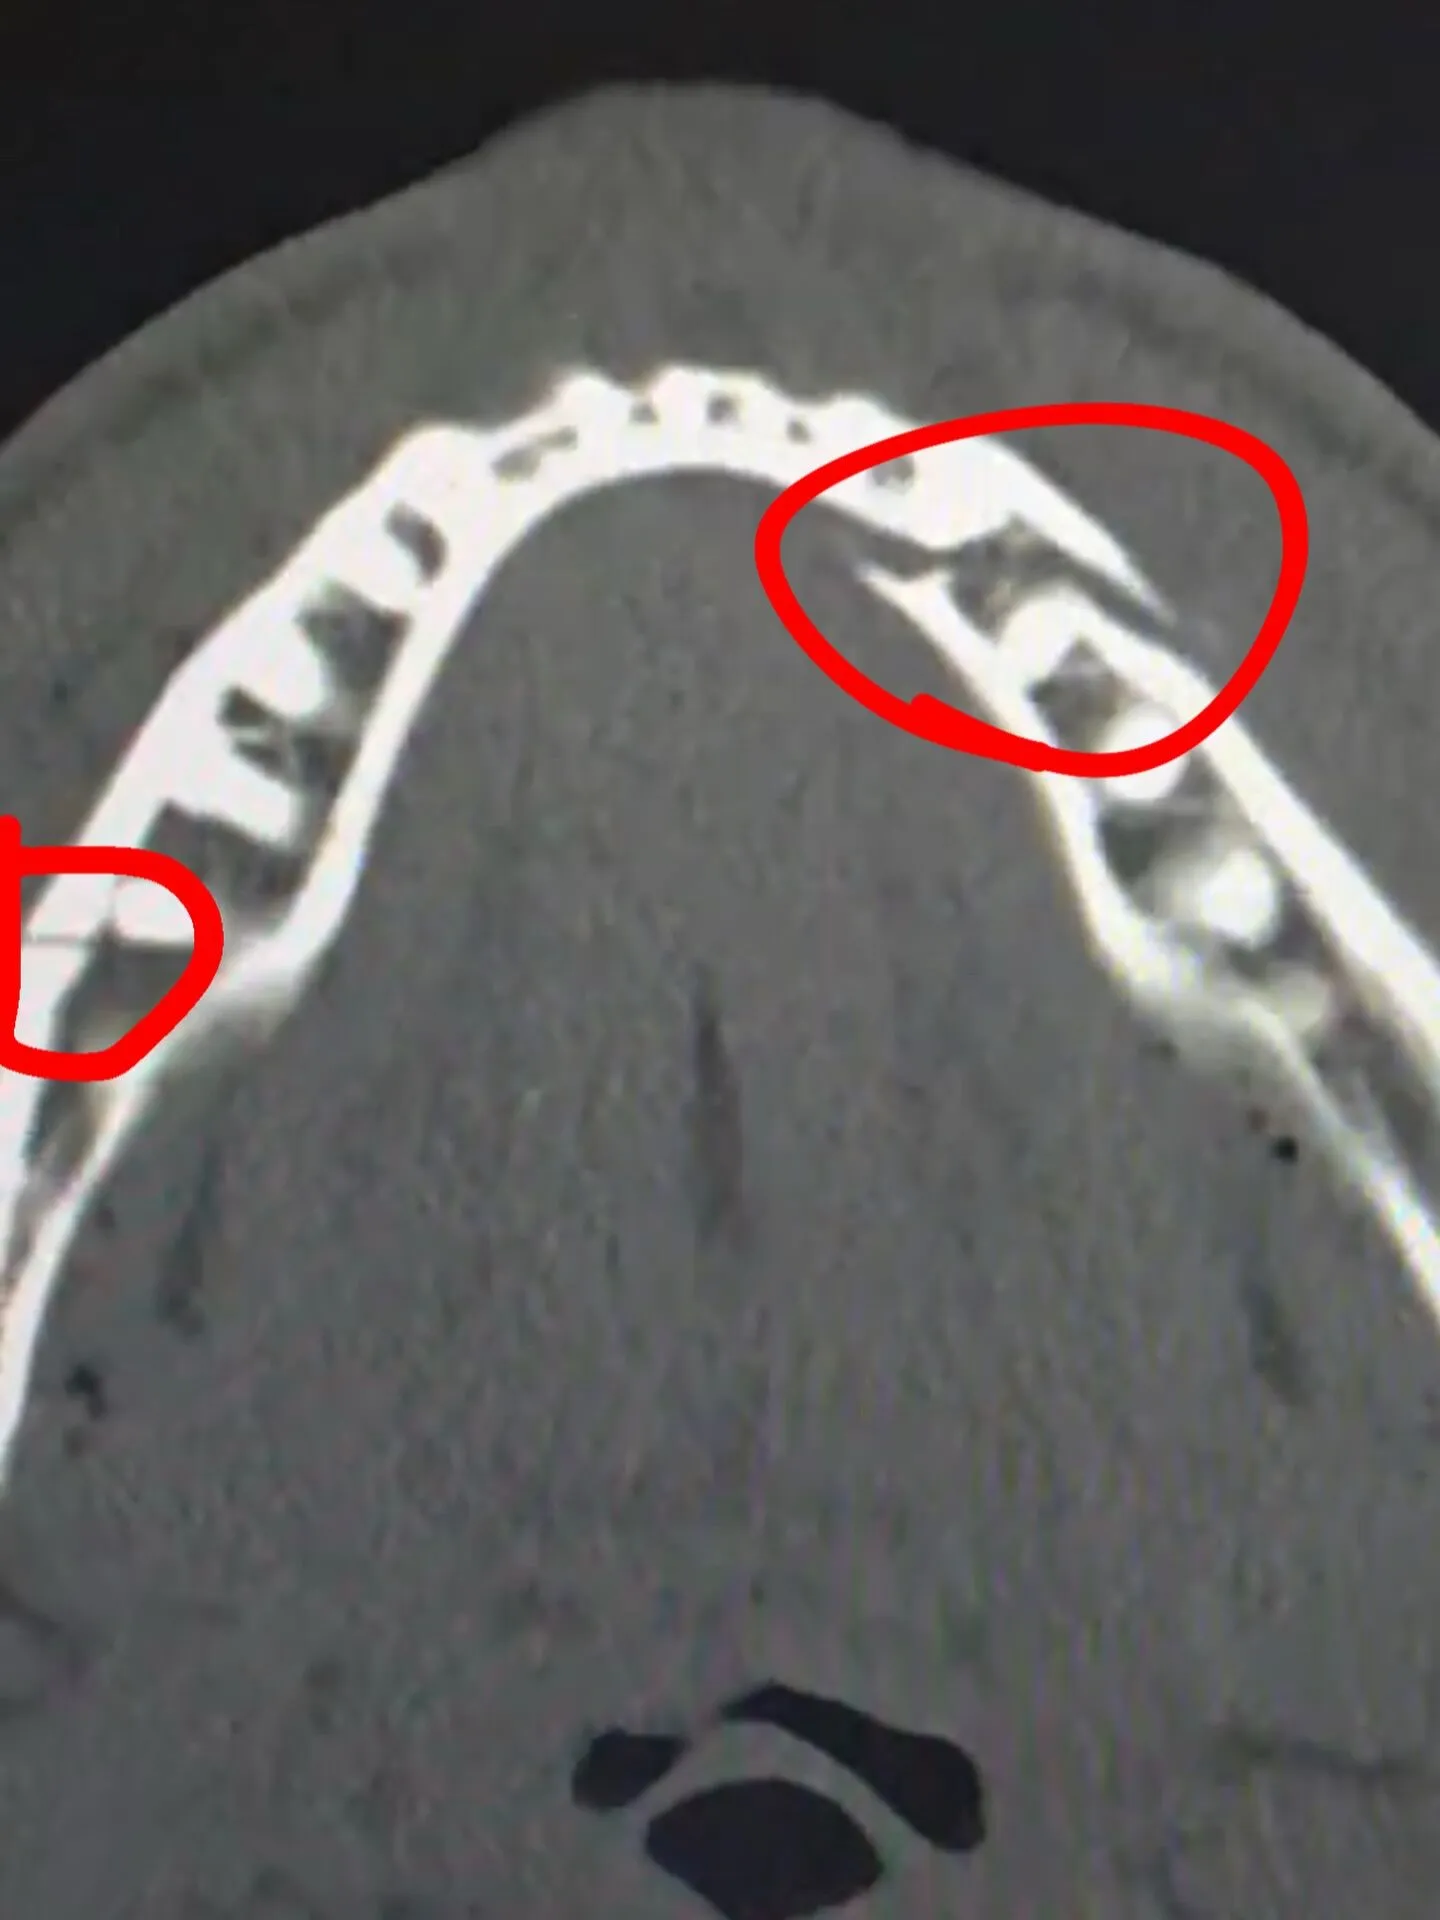

После боя Джейк Пол был доставлен в больницу, где ему диагностировали двойной перелом челюсти.